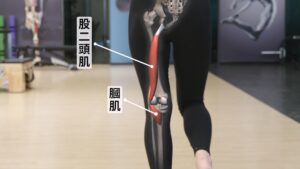

膝蓋後方的膕肌,以及股二頭肌,

這兩條肌肉的肌腱,就特別容易因為過度使用而受傷。

先看第一條:膕肌。

膕肌在膝蓋後側,

從它的位置,我們可以知道,膕肌的起點在股骨,終點在脛骨。

膕肌出力時,可以讓脛骨往內旋。

一旦脛骨卡在外旋,膕肌就會想要出更多力,把脛骨拉回內旋。

結果就是,膕肌一直出力,卻拉不回來,久了就容易發炎。

再來,股二頭肌

股二頭肌是一條從骨盆,連接到脛骨外側的肌肉,可以幫助脛骨做出外旋的動作。

當脛骨無法內旋時,大腿後外側的股二頭肌就容易變緊。

如果長期卡在外旋,這條肌肉就會因為長期缺少伸縮的動作而變得緊繃,讓膝蓋後側的肌腱壓力變大。

你看,膕肌還有股二頭肌,這兩條肌肉的肌腱,在膝蓋後側是不是重疊了。

因為這兩條肌腱重疊的地方,就是你會痛的地方,

這就是為什麼脛骨無法內旋的話,跑久了膝蓋後側痛的原因。